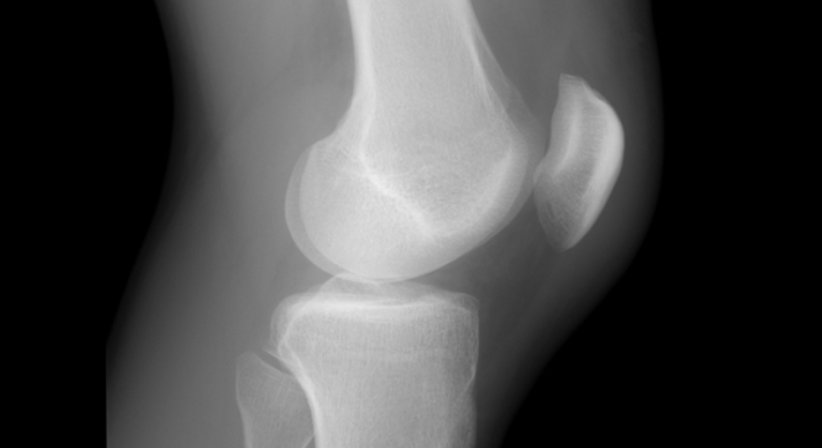

Bei Röntgenstrahlen handelt es sich um energiereiche elektromagnetische Wellen, die in der Lage sind den Körper zu durchdringen und die Organe dadurch abbilden können. Es entsteht dabei keine radioaktive Strahlung.

Röntgenstrahlen sind besonders zur Unters​uchung von Lunge und Knochen geeignet. Mit zusätzlich verabreichten Kontrastmittekönnen auch auch Magen, Darm, Nieren und Gefäße gut dargestellt werden.